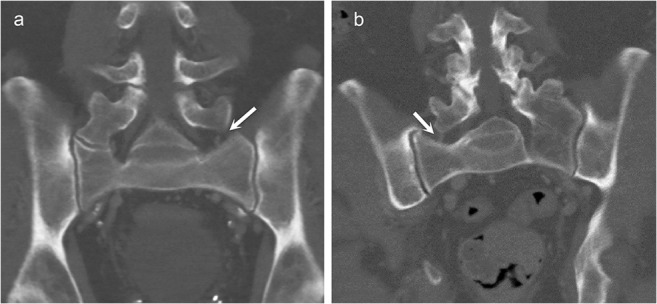

Males and females had type I LSTV in 77% and 54% of all cases; type II 11% and 24%; type III 10% and 18%; and type IV 3% and 4%, respectively (p < 0.001). Additionally, type IIa and IIIa LSTVs with enlarged contralateral transverse process (height greater than 19 mm) were identified in 49 (4.5% of LSTV studies) and 9 (0.8%) studies, respectively. These types have not been included in the classic Castellvi classification during the modern era of imaging. Therefore, they are noted here as types IIc and IIIc as a logical continuum of the Castellvi classification as demonstrated in Fig. 1.

Fig. 1.

The proposed new subtypes to the classic Castellvi classification on coronal CT images. A 63-year-old male with suggested type IIc lumbosacral transitional vertebra (LSTV) showing a pseudoarticulation on the right side and an enlarged transverse process without articulation on the left side (arrow) (a). A 78-year-old male with suggested type IIIc LSTV demonstrating a complete fusion on the left side and an enlarged transverse process without articulation on the right side (arrow) (b)

This is the first large-scale study to evaluate the prevalence of LSTV and to show the association of LSTV with whole lumbar degenerative changes using CT scans. The prevalence of LSTV was 28.6%. Castellvi types III and IV, and especially type II, had greater overall disc and facet degeneration in the lumbar spine compared with type I and the control group. We also observed type IIa and IIIa LSTVs with an enlarged contralateral transverse process and as these have not been described in the classic Castellvi classification, we noted these as types IIc and IIIc, respectively, for consistent addendum to the Castellvi classification.

As CT offers superior resolution to assess bony contours, we noticed that some subjects had nearly fused LSTVs of type II. It appeared that some subjects had a congenital LSTV of type III, whereas some subjects had a LSTV of type III born out of degenerative osteophytic fusion. We also observed types IIc and IIIc which have not been noted in the classic Castellvi classification (Fig. 1). In our opinion, this is rationalized by the logic behind the classic Castellvi classification, as type I has an enlarged transverse process and IIa and IIIa have only either unilateral pseudoarticulation or complete osseous fusion [3]. In fact, the authors are relatively surprised that these subtypes have not been suggested earlier in the modern era of cross-sectional imaging.